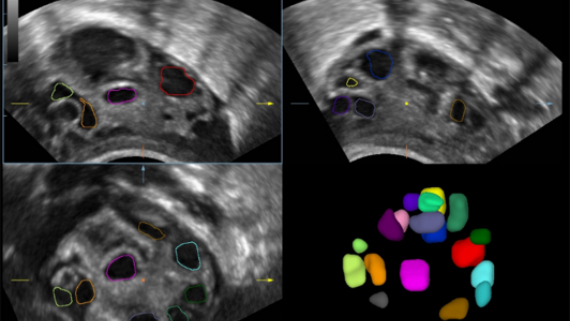

Obrazy kliniczne